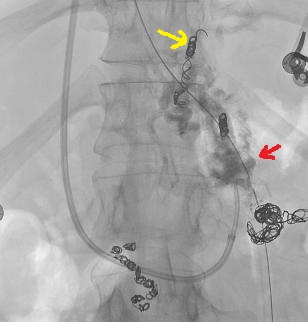

A 35 year old man with partial portal vein thrombosis related to Crohn’sdisease and gastric varix Prophylactic BRTO of gastric varixdue to continuing anticoagulation therapy